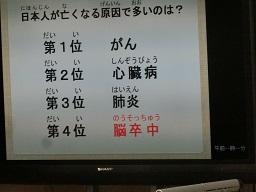

今日の2時間目に6年生が脳卒中の勉強をしました。今、日本で4番目の死亡原因です。

テレビを使って分かりやすく教えてもらいました。写真がもう少しありますので後日続きをお知らせします。